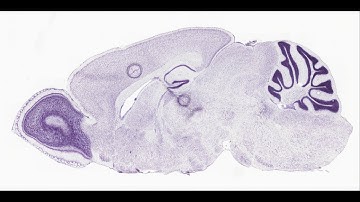

RGB Serial Section Mouse Brain